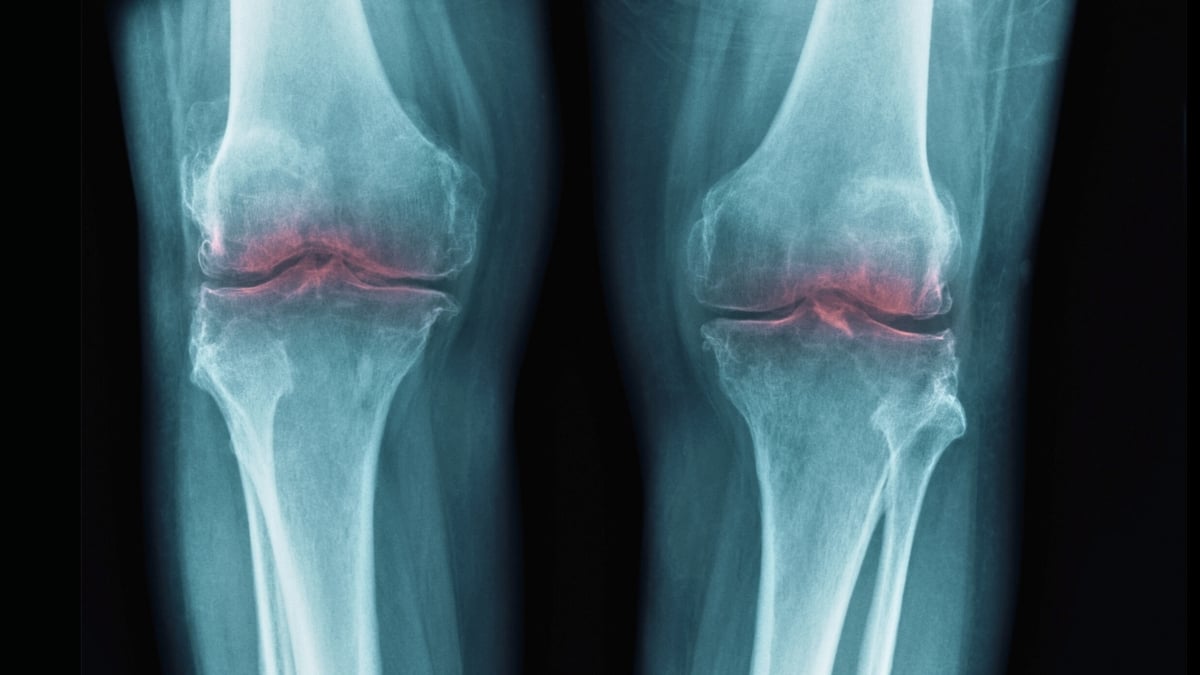

That led researchers at Stanford University to consider whether 15-PGDH might be involved in osteoarthritis, in which joint stress leads to the breakdown of cartilage collagen, causing inflammation and pain.

In tests on old mice, knee cartilage that had previously worn down thickened following the introduction of a 15-PGDH inhibitor. In similar tests on young, injured mice, the inhibitor protected against the typical effects of injury-induced osteoarthritis.

The same experiment was also conducted on human tissue samples from people undergoing knee replacement surgery. Again, there were clear signs of regeneration, with the cartilage becoming stiffer and showing less inflammation.